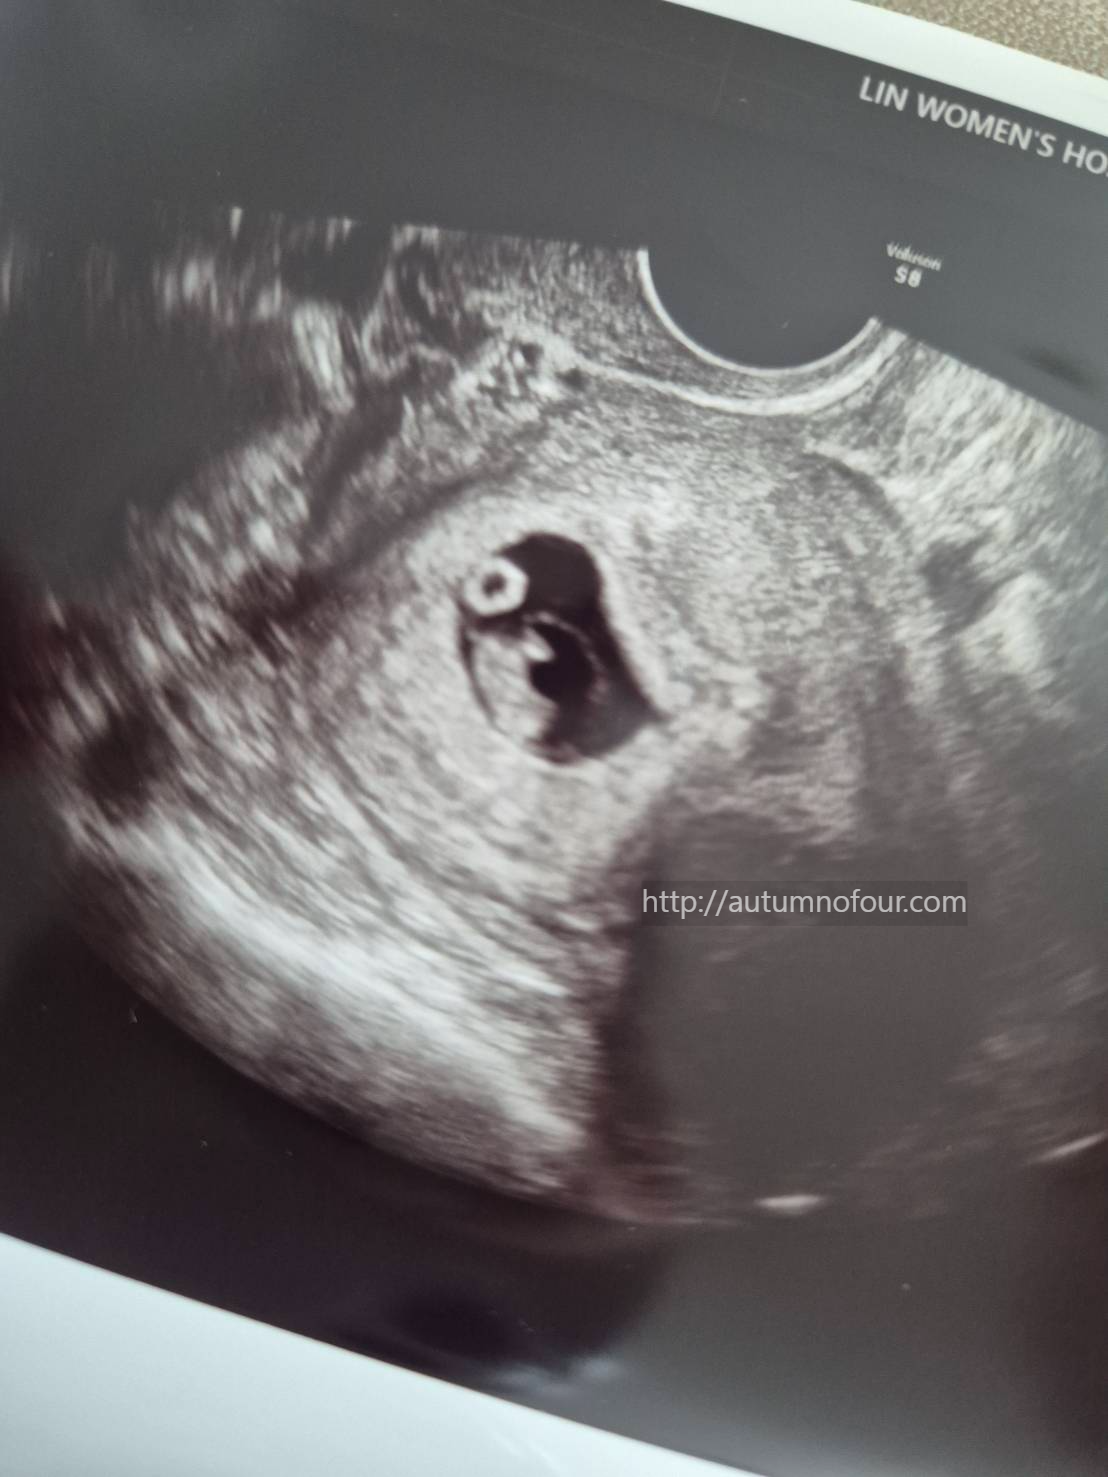

그리고 오늘은 특별히 실시간으로 초음파 화면을 보여주셨다.

지난주엔 난황만 확실히 보이고

아기는 어디있다는건지 알 수가 없었는데

일주일 사이에 존재감이 커졌다.. !!!!

그리고 쿵쾅쿵쾅 심장소리까지... !

신기해 신기해 신기해

3. 진료실에 있는 화면으로 남편도 실시간으로 초음파로 아기를 보고 심장소리를 들었다.

심장소리도 좋고 아주 잘 크고 있다는 이야기를 들었다.